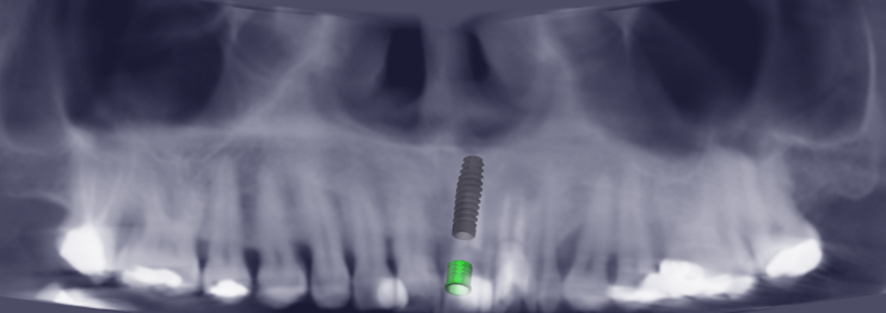

Radiografia Periapical inicial para auxilio no diagnóstico.

Planejamento de melhor posicionamento tridimensional do implante.

Rádiografia Periapical final.